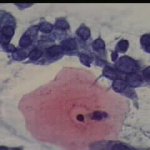

Εικονες φυσιολογικών και παθολογικών κυττάρων ενδοτραχήλου κι ενδομητρίου στο επίχρισμα κατά Papanicolaou. Περιστατικά ιατρείου. Παρατίθενται για τις ανάγκες επίδειξης περιστατικών στο forum του www.gyn.gr, για φοιτητές εργαστηριακών παραϊατρικών επαγγελμάτων και για καθε άλλο ενδιαφερόμενο.